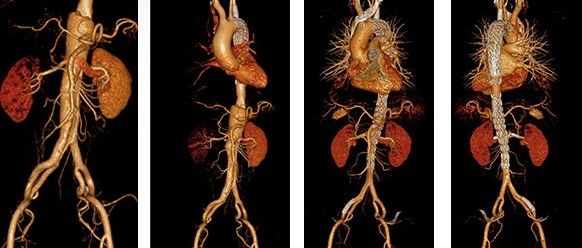

2022 CEC | 张鸿坤:打破壁垒,挑战内脏区——顺行原位开窗全腔内修复胸腹主夹层动脉瘤